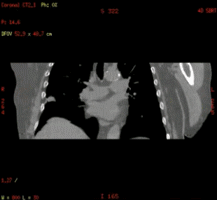

双侧髋关节置换术后(Smart MAR可以减少金属伪影)